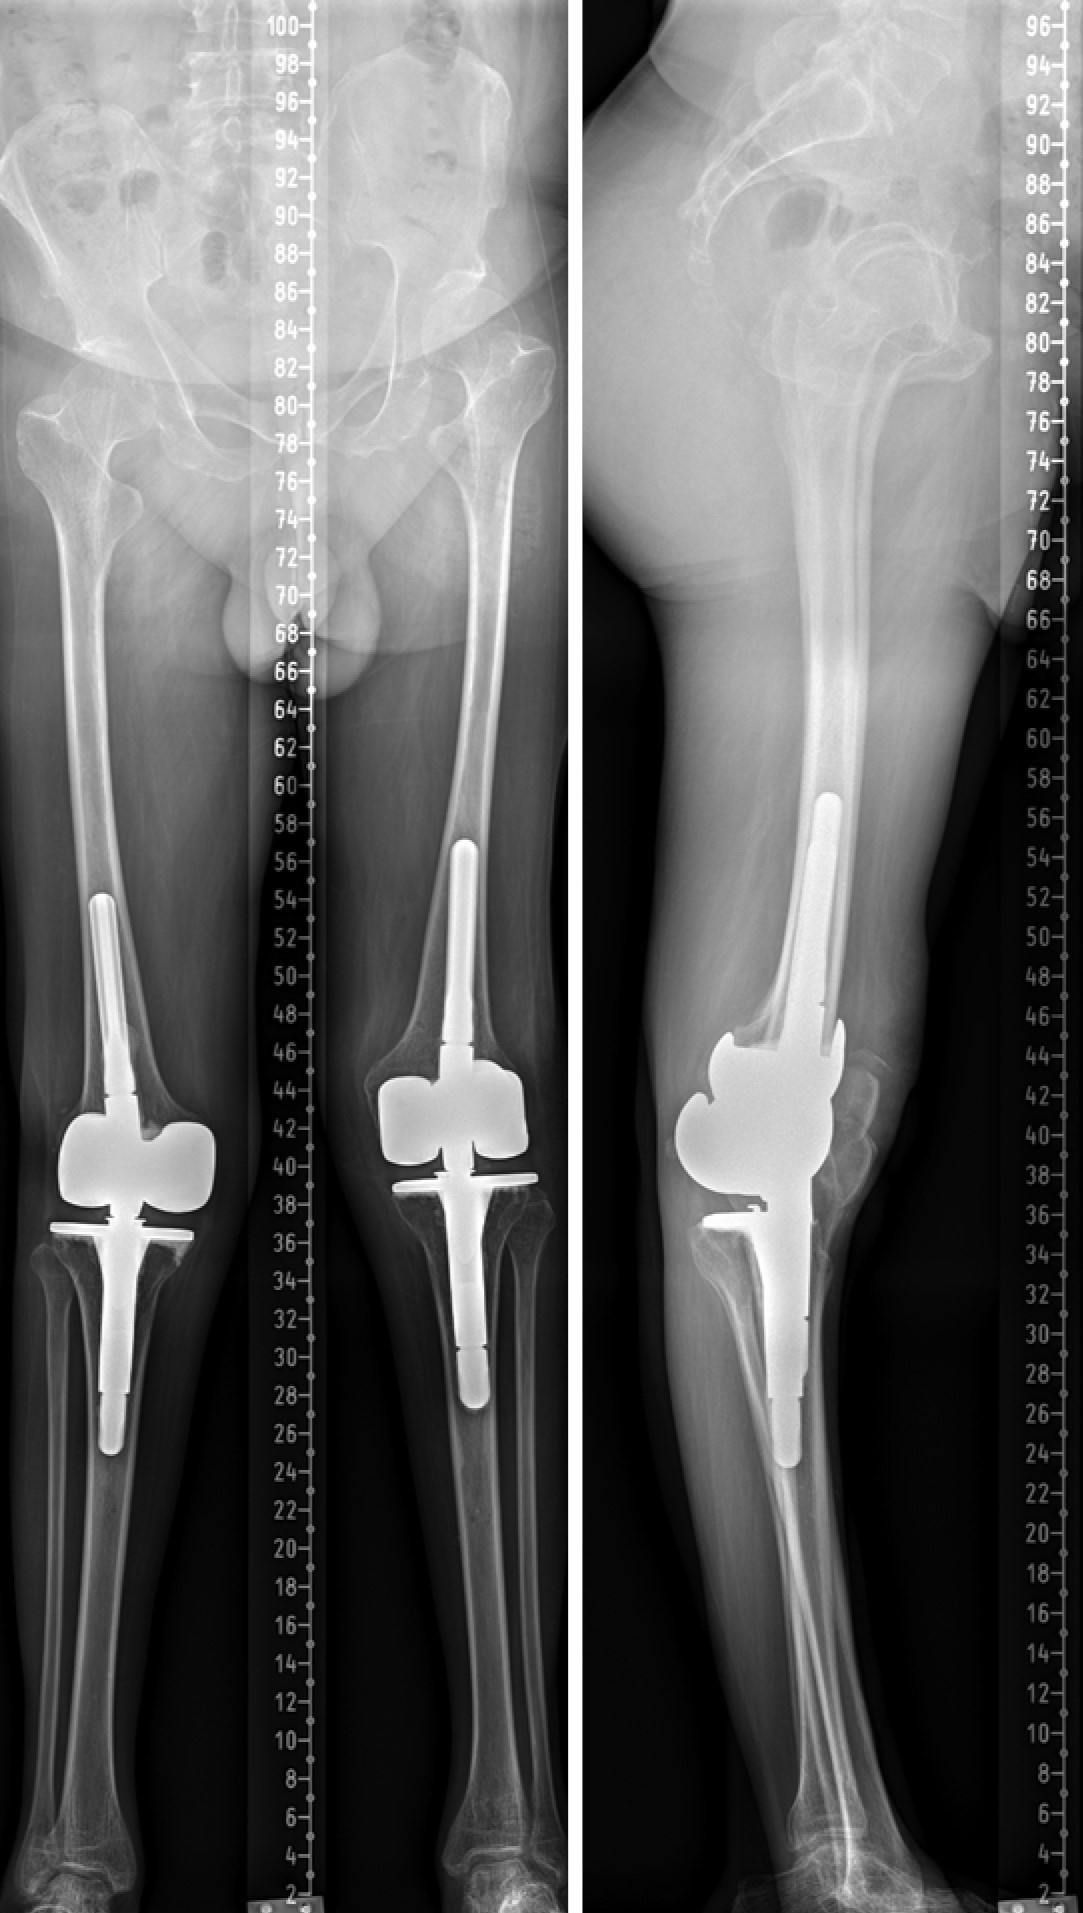

Послеоперационный период после второго этапа был проведен аналогично предыдущему. Течение раневого процесса и активизация проходили соответственно срокам и объему проведенного оперативного вмешательства. Пациент был выписан на амбулаторный этап лечения, рана зажила первичным натяжением, швы сняты в стандартные сроки (рис. 10). В сроки 3, 6, 12 мес. и далее раз в год после операции пациенту выполняли контрольные рентгенограммы, оценивали его объективный и субъективный статуса.

Рис. 10. Телерентгенограммы пациента после второго этапа операции

Figure 10. The patient’s long film X-rays after the second stage of the surgery

На момент написания данного материала сроки наблюдения составляли 4 года (рис. 11). Пациент ходит с полной нагрузкой. Амплитуда пассивных движений в обоих коленных суставах составляет около 130°. Рецидивов нестабильности и гиперэкстензии не наблюдается. В качестве дополнительной опоры пациент использует трость при длительных прогулках. Походка соответствует стереотипу для пациентов с гиперэкстензией вследствие перенесенного полиомиелита, однако он может передвигаться без дополнительной опоры в помещении.

Рис. 11. Ренгтенограммы через 4 года с момента второго этапа операции

Figure 11. X-rays taken over a period of 4 years after the second stage of the surgery

Субъективно пациент оценивает результаты проведенных операций как отличные. При оценке по опроснику KSS сумма баллов составляет 88, что также соответствует отличным результатам.